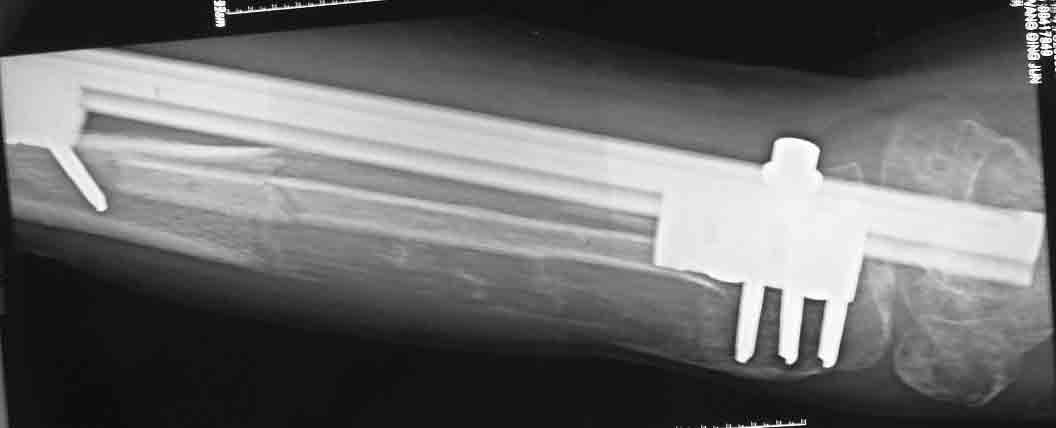

下图  X线片显示,左胫骨延长区骨质稀疏,透光度高,延长截骨平面在关节面下5厘米。